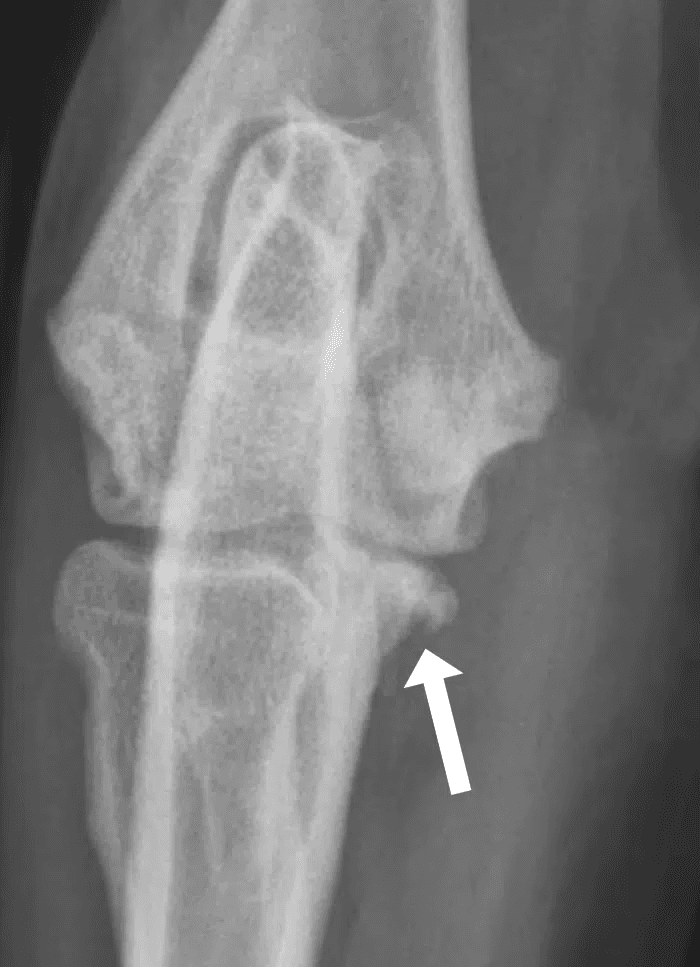

FMCP

Fragmentation of the Medial Coronoid Process (FMCP): A small bony prominence on the ulna fractures, creating a loose fragment that irritates the joint and accelerates cartilage wear.